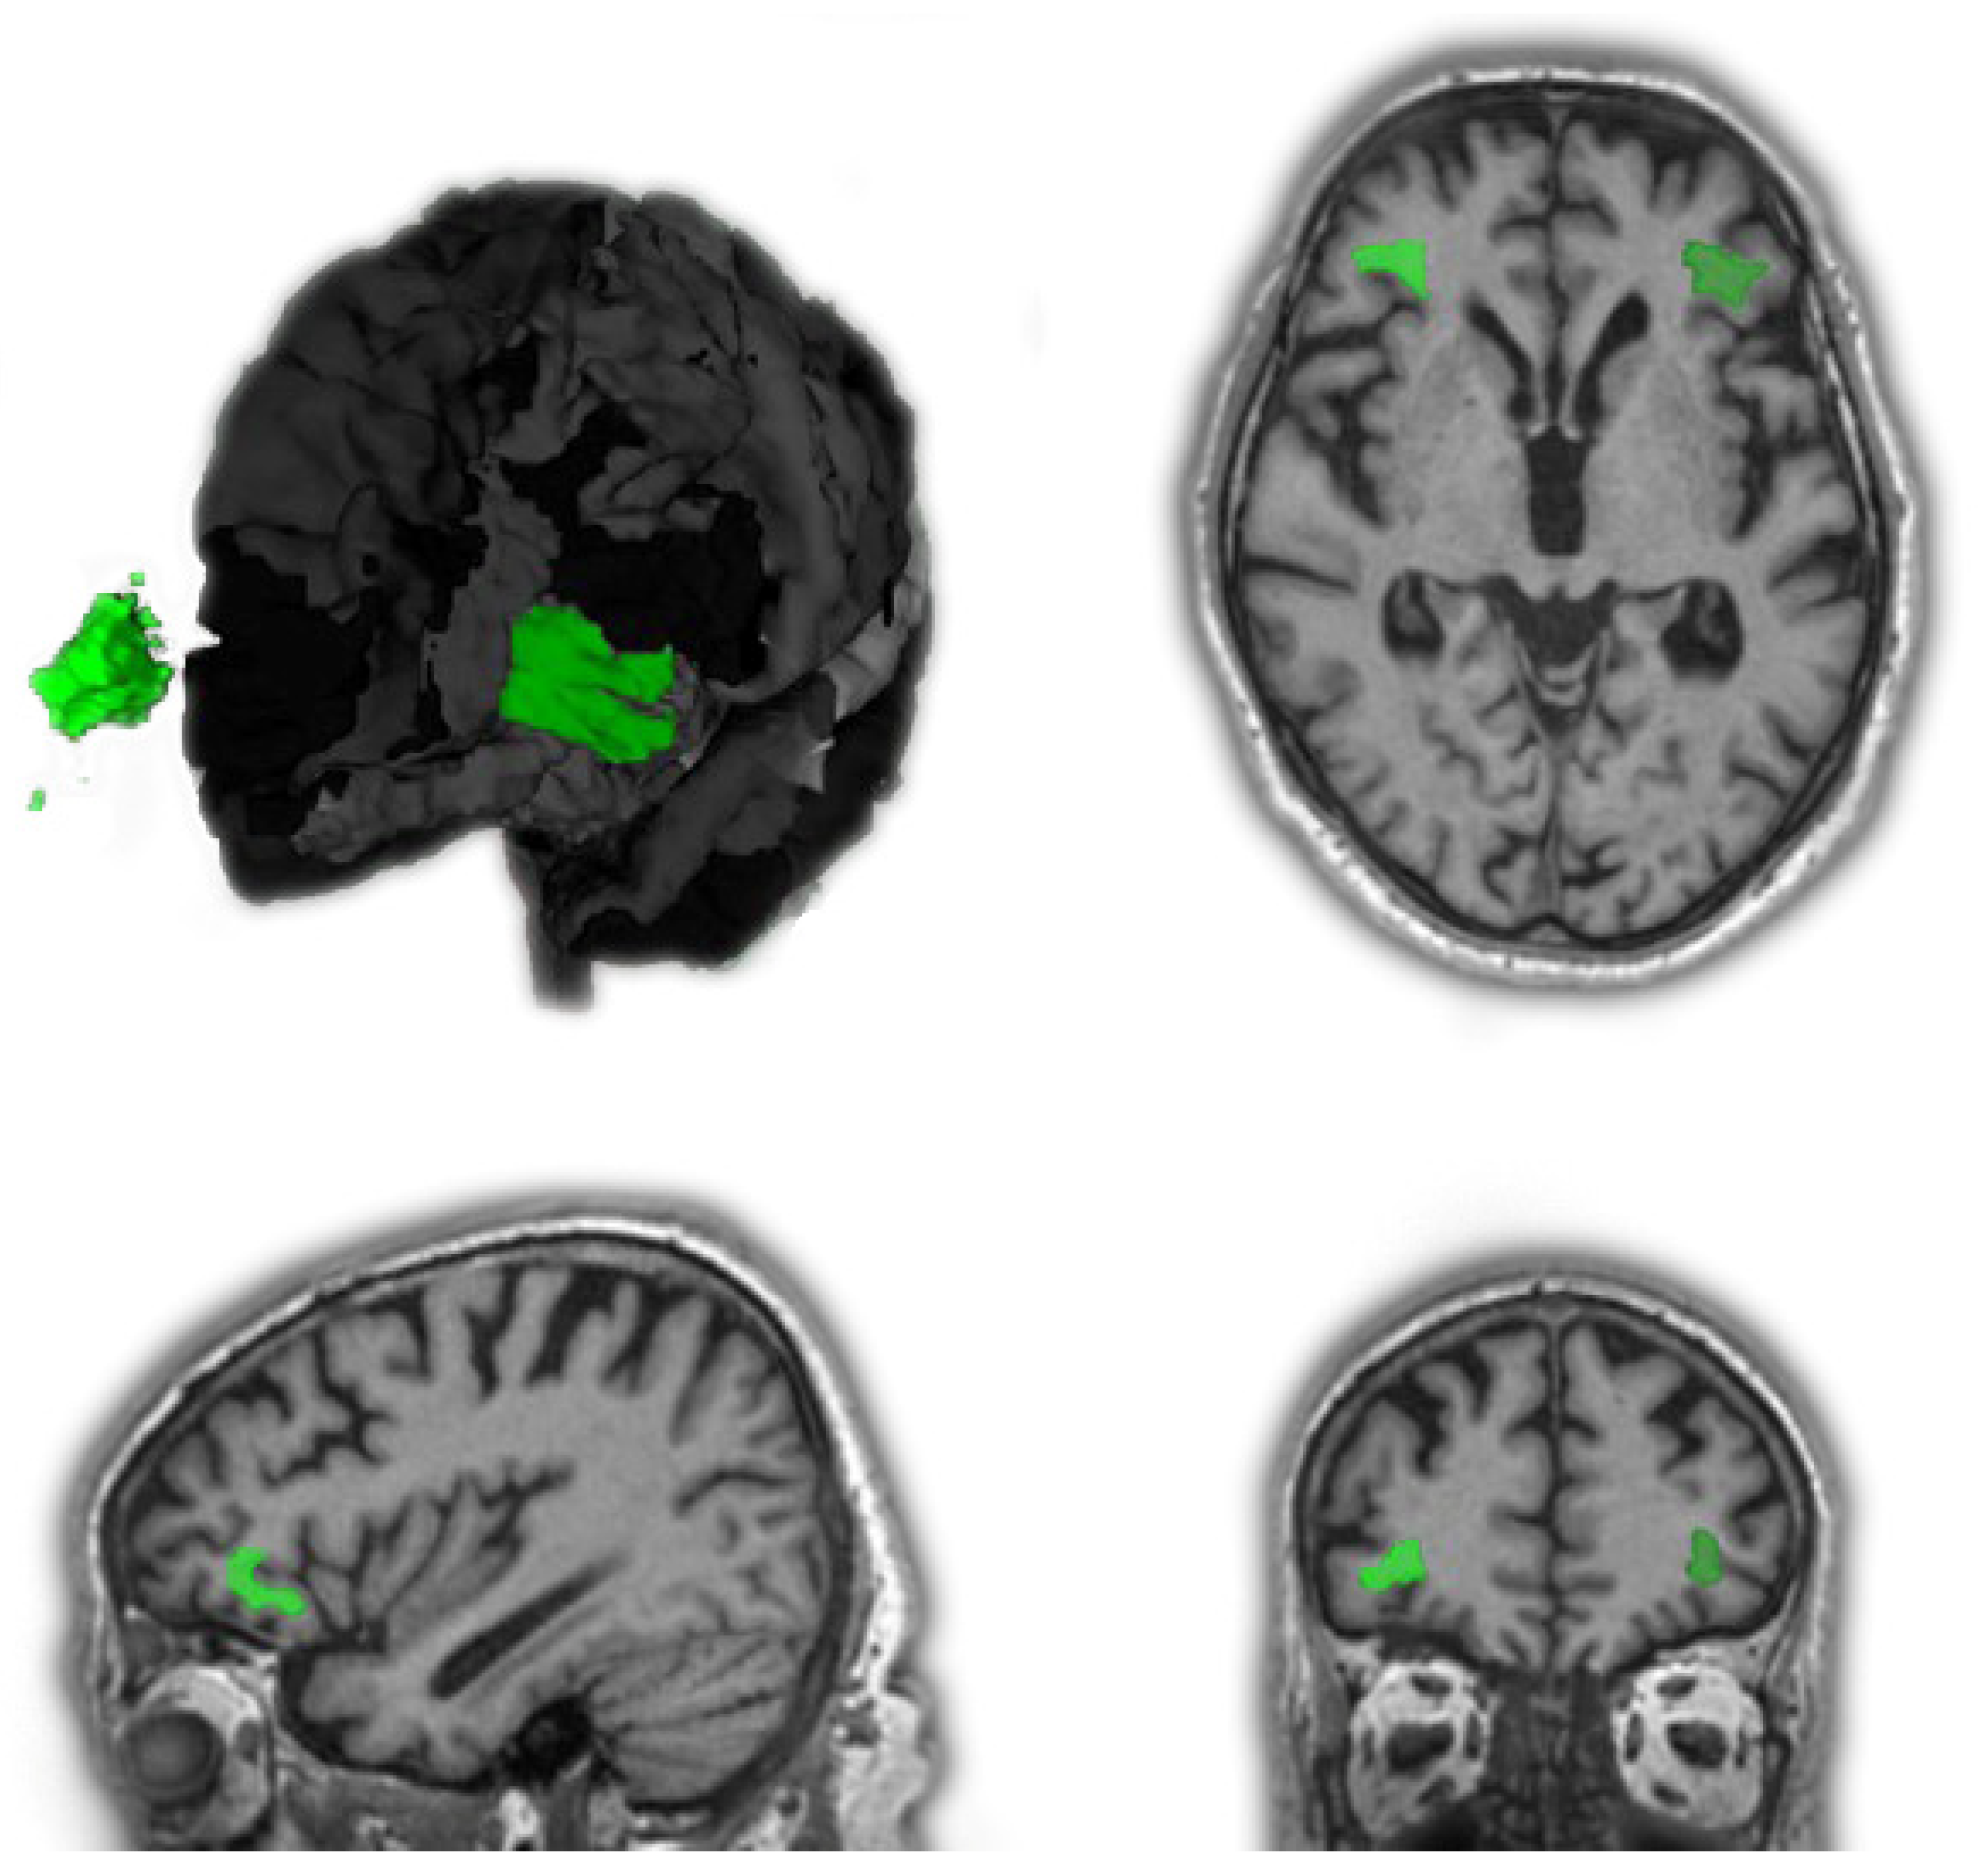

3.2.1. Patients with FTD